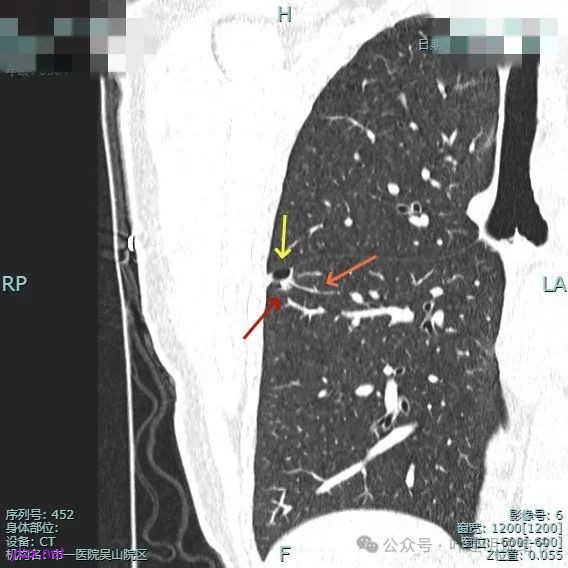

非薄层平扫上这个层面比较明显,似一囊腔,壁厚薄欠均匀。

薄层上看病灶贴着叶间裂与胸膜,此层囊壁薄,囊腔明显。

囊壁局部有增厚。

囊壁局部较厚,但囊壁内也是有小空泡的,病灶贴着胸膜。

病灶部分囊壁是混合磨玻璃成分的,整体轮廓较清。

边缘区也有偏实性成分,磨玻璃成分也还是明显的,有微小血管进入。